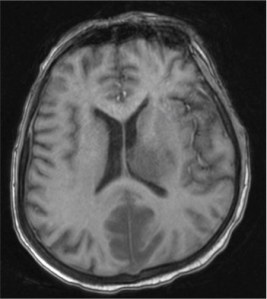

A middle-aged man presented with acute lymphoblastic leukemia (initial white cell count of 150,000 per cubic millimetre of blood – mostly blasts). After completing a course of hyper-CVAD, he developed persistent febrile neutropenia that was unresponsive to antibiotics. On the 6th day of fever, CT thorax was performed which was normal. On the 8th day of fever, he suddenly became drowsy and an MRI brain was performed. Sample images are shown below.

He was brought down to the intensive care unit (ICU) in view of his drowsiness and the brain lesions, and a skin lesion appeared over his face the following day.